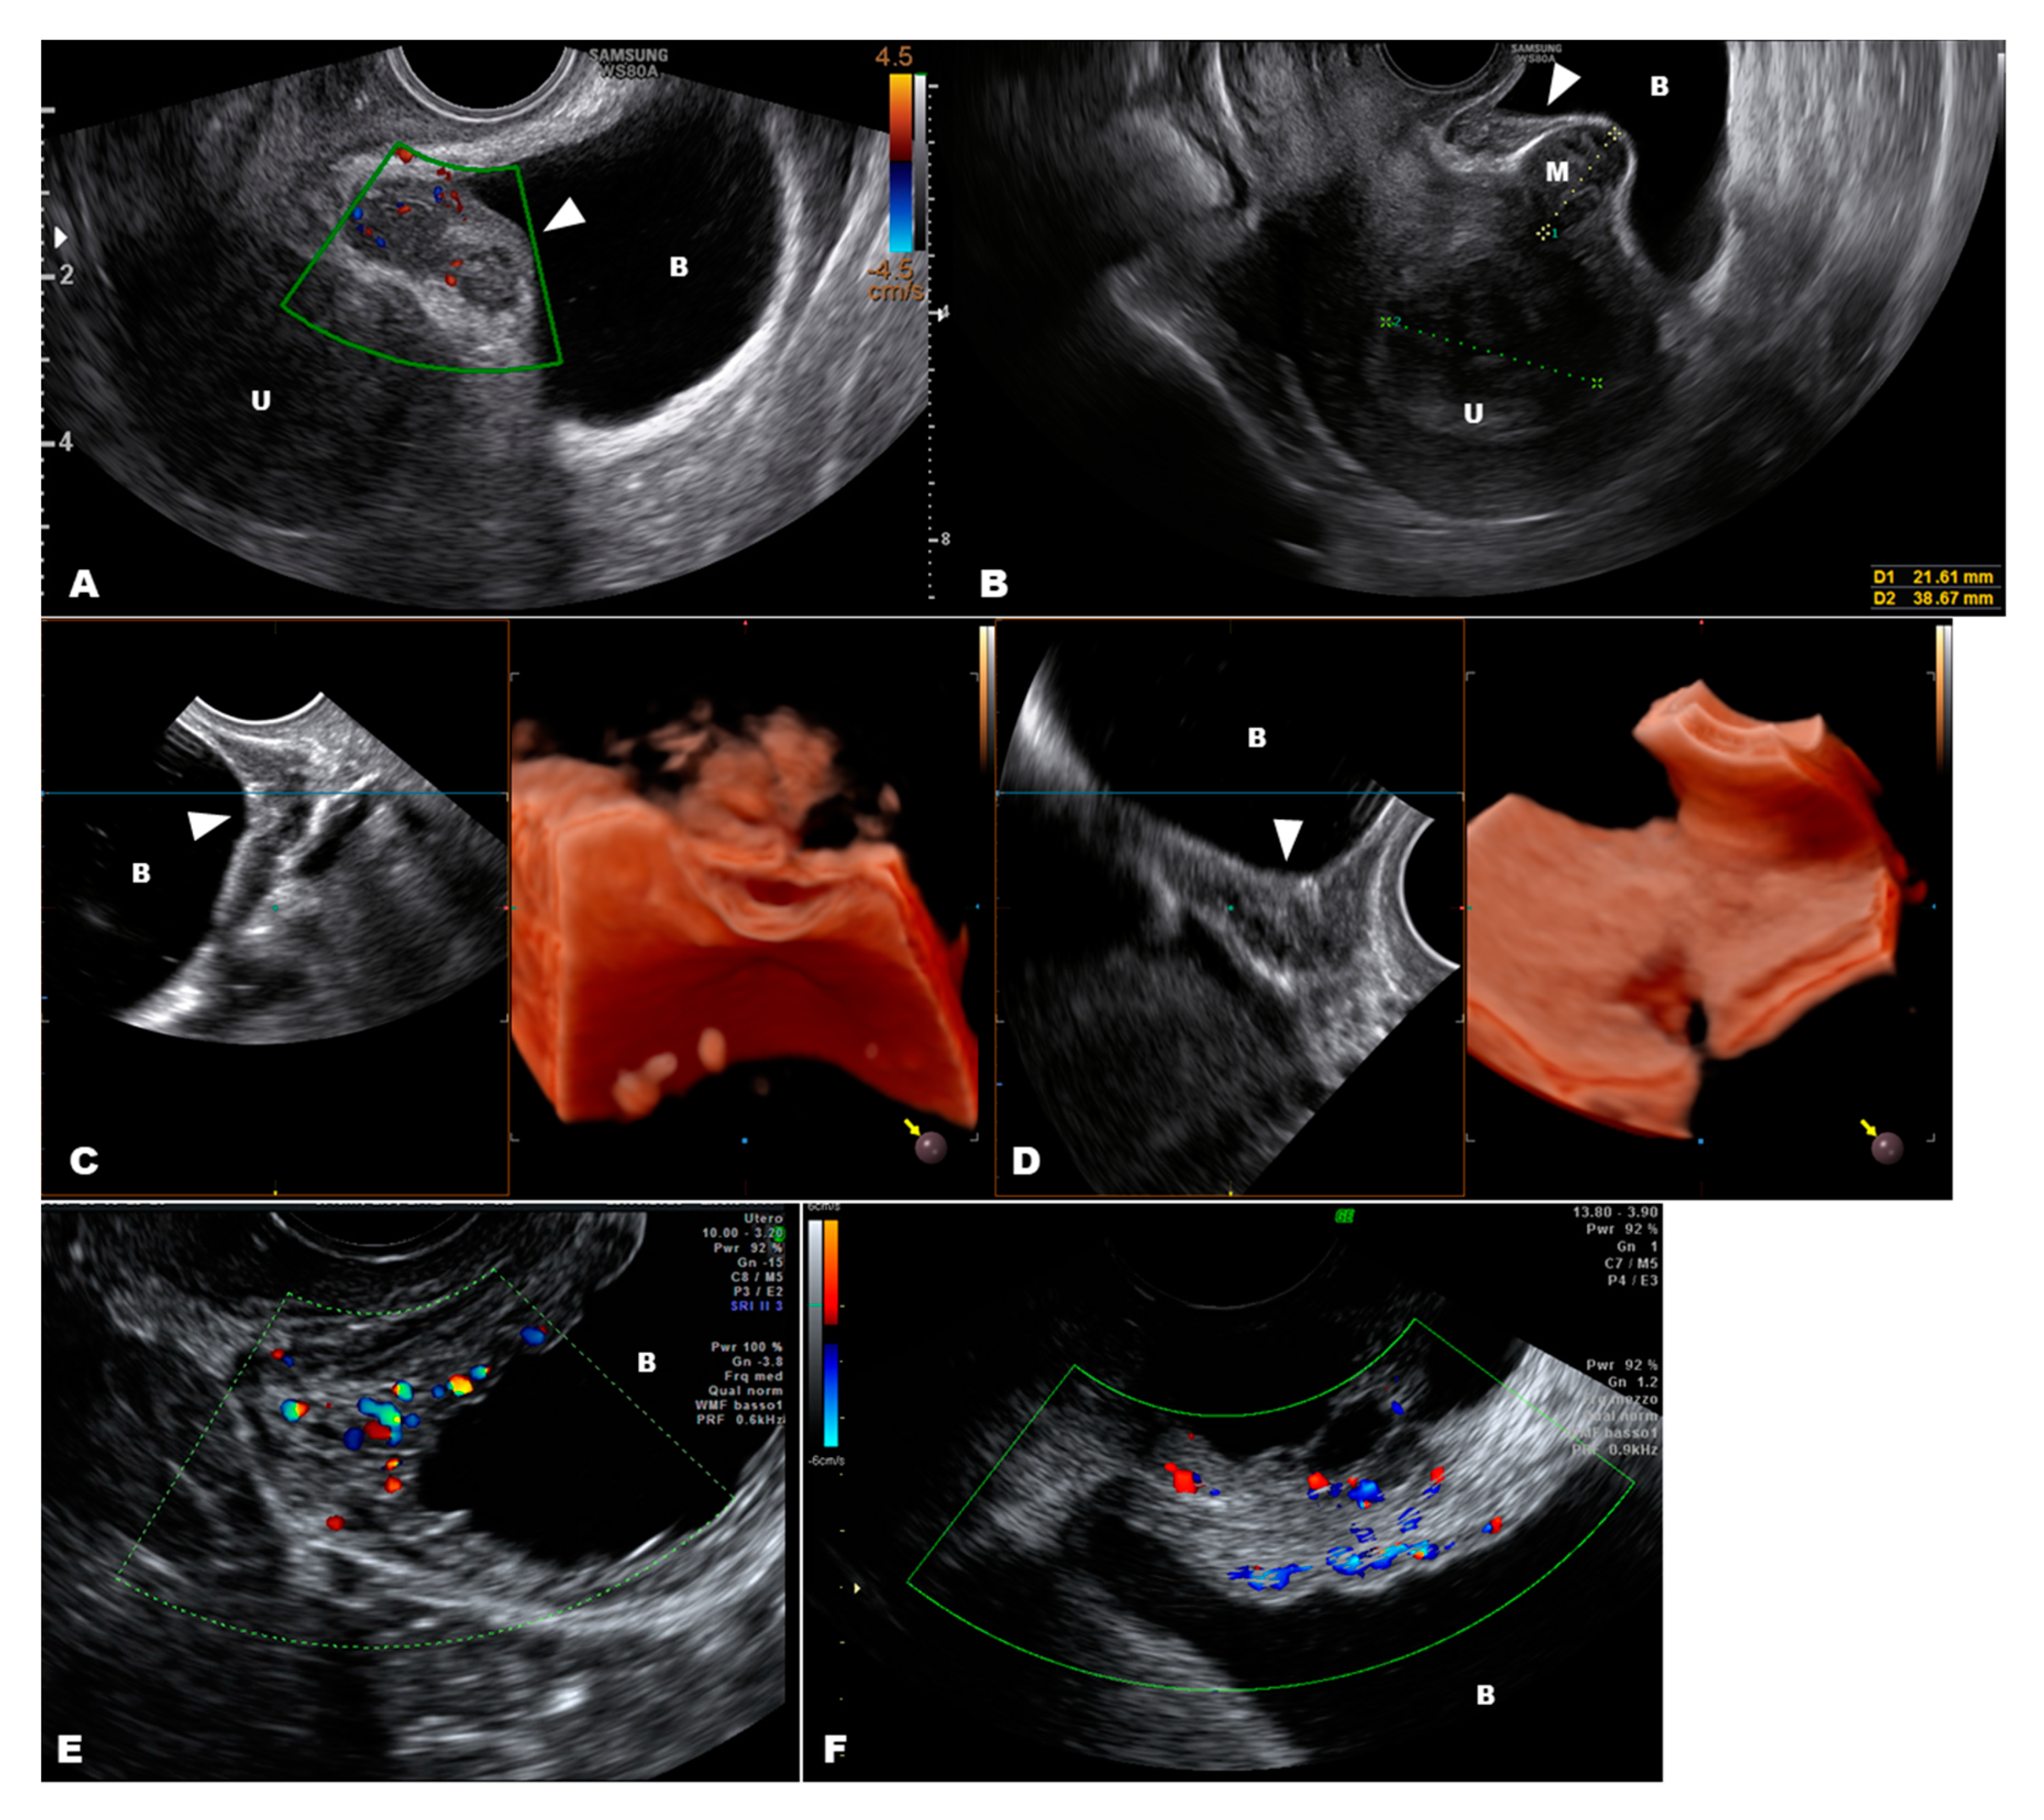

We recently reviewed the DD of urinary tract endometriosis [50]. The DD may sometimes be difficult due to the presence of external masses that encroach the bladder dome (i.e., uterine fibroids or an attached small bowel from a previous surgery, such as a cesarean section), an intravesical ureterocele that may resemble deep lesions of endometriosis, or hypertrophic areas of the bladder wall due to a chronic, complete cystocele and recurrent cystitis [50]. In such cases, although bladder endometriosis very often appears as an endophytic lesion, it may sometimes appear flat and may be confused with hypertrophic areas due to chronic mechanical trauma (cystocele) or recurrent cystitis (Figure 5).

Figure 5.

A typical endometriosis nodule (arrow) of the bladder (A); figure (B) shows a flat nodule of endometriosis (arrow) with a subserosal myoma that distorts the bladder dome; a flat endometriosis nodule (arrow) of the bladder that can be seen at 3D ultrasound only when cut (C) while the internal surface of the bladder appears regular (D); figure (E) shows a thick bladder wall due to cystocele and figure (F) in case of recurrent cystitis. Abbreviations: U, uterus; B, bladder; M, myoma.